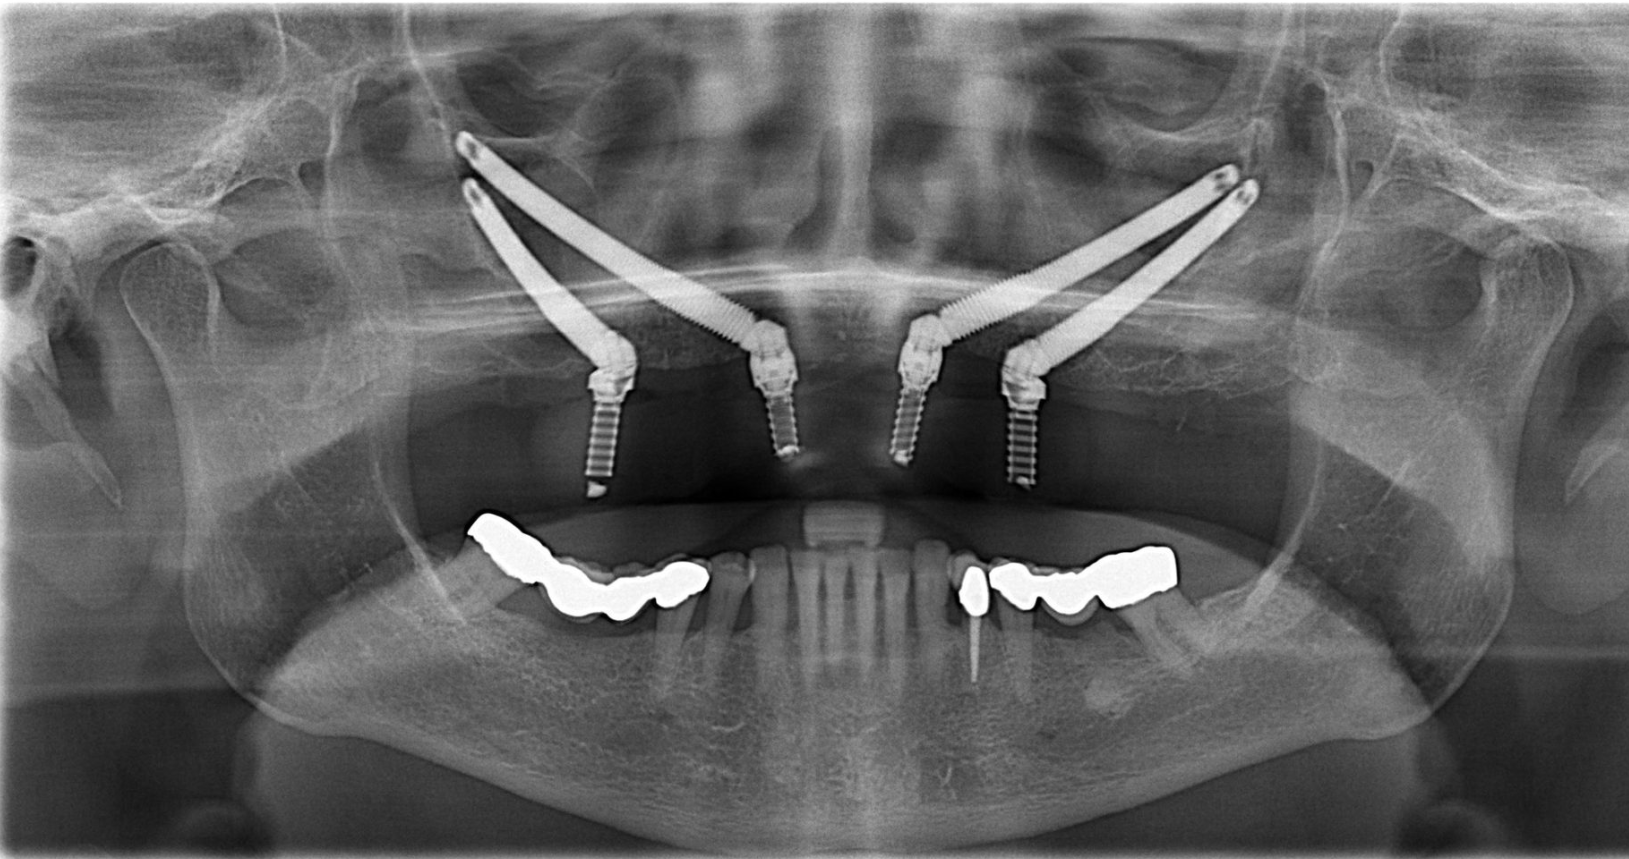

Implant Zygoma (Implant xương gò má) là loại trụ Implant dài từ 30mm đến 52mm, được thiết kế để cấy trực tiếp vào xương gò má (xương zygoma). Khác với Implant thông thường chỉ dài 8-13mm và cấy vào xương hàm, Zygoma bỏ qua vùng xương hàm trên đã tiêu, neo chắc vào xương gò má vốn rất đặc và ổn định.

- Chụp Cone Beam CT 3D, đánh giá mật độ xương gò má và xoang hàm.

- BS Võ Tá Dũng lập kế hoạch 3D chi tiết, xác định góc và vị trí trụ Zygoma.

- Tiền mê hoặc gây mê toàn thân (tùy ca), Phẫu thuật cấy trụ Zygoma kết hợp trụ thường.

Phẫu thuật Implant Zygoma đòi hỏi bác sĩ có tay nghề chuyên sâu về Implant phức tạp. Tại Thế Giới Implant, BS Võ Tá Dũng trực tiếp thực hiện tất cả ca Implant Zygoma.